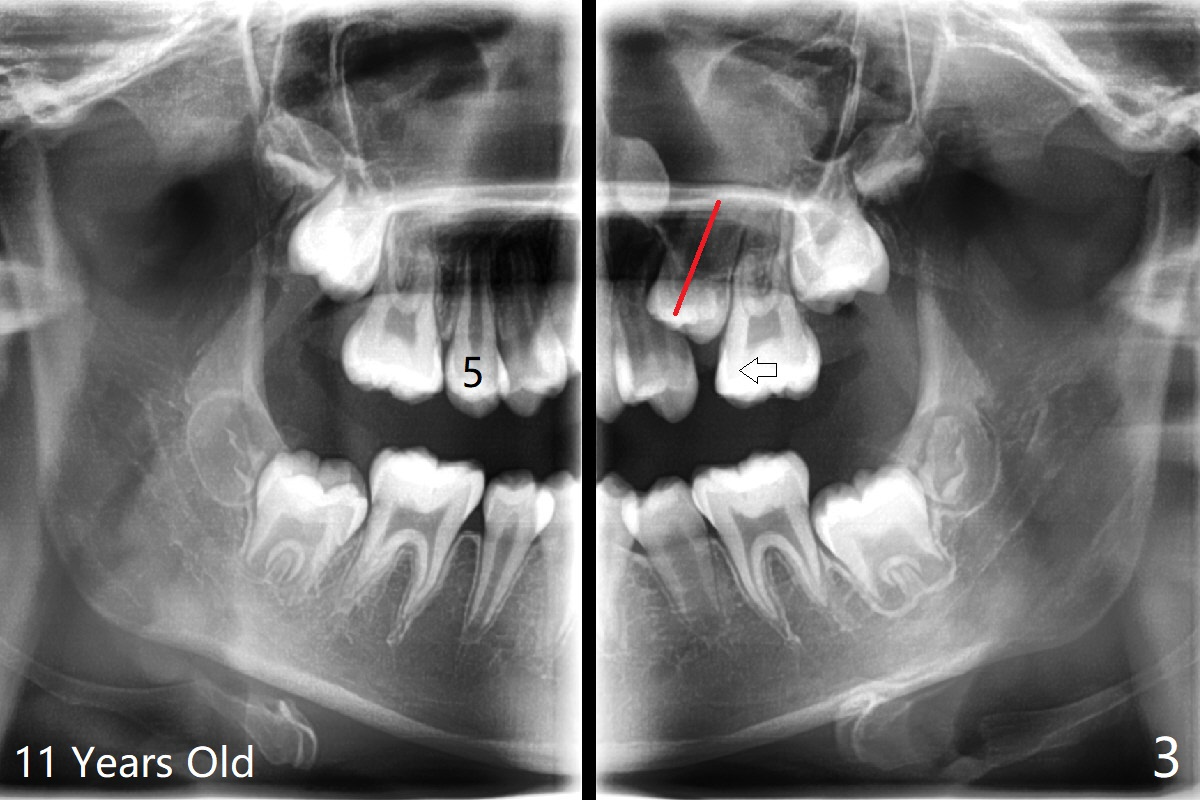

一位女孩具有家族性牙齿拥挤史,6岁下中切牙刚萌出时就显示拥挤(图一),九,十一岁相当明显(图二,三),十一岁正好处于新冠病毒流行期间,妈妈同意拔除四个第一双尖牙,让牙列自行调整一年左右。初步检查表明上下磨牙近远中位置正常。不紧不慢使用弓丝排列牙弓,让7充分萌出。牵引上尖牙时,注意磨牙位置改变,最好同时使用下6(二类牵引)以及上5-7作为支抗。